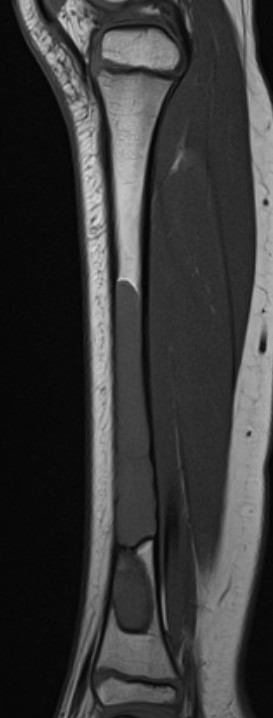

MRI

Gruenewald et al Br J Radiol 2023

- 36 patients with UBC or ABC

- fluid fluid levels / septation seen in both

- arterial feeders on MRA helped differentiate some ABC's